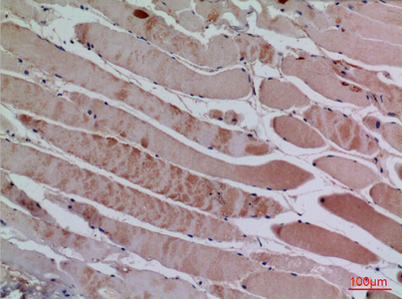

Product name: BLC rabbit pAb

Dilutions: Western Blot: 1/500 - 1/2000. IHC-p: 1:100-300 ELISA: 1/20000. Not yet tested in other applications.

Immunogen: The antiserum was produced against synthesized peptide derived from the Internal region of human CXCL13. AA range:41-90